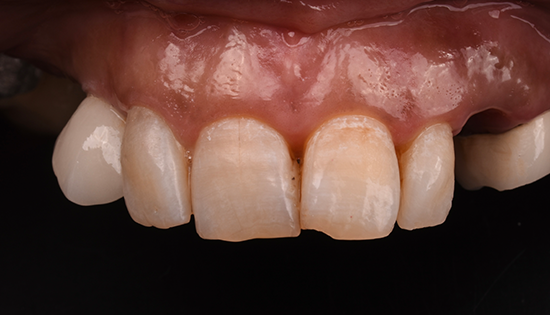

يلجأ الشخص إلى تحسين شكل أسنانه عن طريق فينير الأسنان أو ما يطلق عليه (عدسات الأسنان اللاصقة) وهي عبارة قشرة رقيقه يتم لصقها على السطح الخارجي للأسنان مصنوعة من مواد صلبة ذات معامل شفافيه مطابق للأسنان الطبيعيه   لعلاج مشكلة الاصفرار أو عدم التساوي والعديد من المشاكل الأخرى، حتى يحصل الشخص على ابتسامة رائعة تشبه ابتسامة نجوم هوليود.

•  تغير لون الأسنان الطبيعية من اللون الأبيض للون الأصفر.

• وجود مسافات بين الأسنان.

• تكسر وتشقق الأسنان.

• عدم تناسق الأسنان او اعوجاجها.